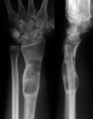

On radiographs, streaks of low density are seen projecting through the diaphyses into the epiphyses of the long bones, due to ectopic cartilage deposits. With age, the cartilage may calcify in the typical "snowflake" pattern.

X-ray showing calcified enchondromas localized in finger a 37-year-old patient affected with Ollier disease

X-ray showing enchondromas localized in the lower part of the radius of a 37-year-old patient affected with Ollier disease